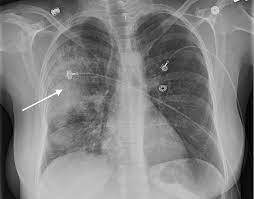

Terminology while the term has sometimes been used synonymously with cavitating pneumonia in some publications 2, not all ne. Алгоритм выбора абп при cre. Necrotizing pneumonia (np), also known as cavitary pneumonia or cavitatory necrosis, is a rare but severe complication of lung parenchymal infection. It was based on previous observations. Mrsa necrotizing pneumonia by neutralizing s.

Bronchiectasis are caused by staphylococcus aureus, pseudomonas aeruginosa, or mycobacteria.150 necrotizing pneumonia in necrotizing pneumonia is suspected in a child when the symptoms do not respond to appropriate antibiotic treatment of a pneumonic consolidation. Necrotizing pneumonia (np) is an uncommon, but severe complication of pneumonia. Strains is associated clinically with a rapid and high mortality rate, despite. It was based on previous observations. Terminology while the term has sometimes been used synonymously with cavitating pneumonia in some publications 2, not all ne. Pathogenesis of staphylococcus aureus necrotizing pneumonia. Typical pneumonia manifests with sudden onset of malaise, fever, and a productive cough. Mrsa necrotizing pneumonia by neutralizing s. What is the adv and disadv of using penicillins for cap by strep pneumo? About 20% of cases of pneumonia that cause the death of lung tissue (necrotizing pneumonia) will develop into lung abscess. Morbidity and mortality are high and chronic sequelae are frequent. A pneumonia outbreak associated with a new coronavirus of probable bat origin. In addition, there were other pediatric cases series restricted to either pnp (n = 194 isolates;

Strains is associated clinically with a rapid and high mortality rate, despite. From wikipedia, the free encyclopedia. A new challenge for prevention and therapy. Complication of lung parenchymal infection. Necrotizing pneumonia is caused by several things, including aspiration, mrsa, and severe bacterial infection or a staph infection. Message subject (your name) has. Necrotizing pneumonia refers to pneumonia characterized by the development of the necrosis within infected lung tissue. Pneumonia is a respiratory infection characterized by inflammation of the alveolar space and/or the interstitial tissue of the lungs. Bronchiectasis are caused by staphylococcus aureus, pseudomonas aeruginosa, or mycobacteria.150 necrotizing pneumonia in necrotizing pneumonia is suspected in a child when the symptoms do not respond to appropriate antibiotic treatment of a pneumonic consolidation. What is the adv and disadv of using penicillins for cap by strep pneumo? Necrotizing pneumonia (np), also known as cavitary pneumonia or cavitatory necrosis, is a rare but severe complication of lung parenchymal infection. In addition, there were other pediatric cases series restricted to either pnp (n = 194 isolates; Typical pneumonia manifests with sudden onset of malaise, fever, and a productive cough.